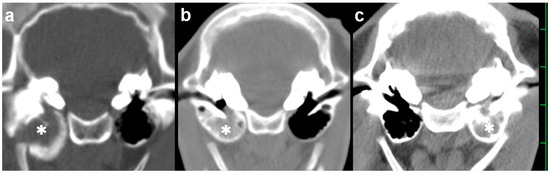

The animal was positioned in dorsal recumbency with the neck extended via a cushion beneath it. A 15 cm incision was made longitudinally in the right paramedian cervical skin caudally to the medial level of the angle of the mandible (Figure 3a). Through blunt dissection of the subcutaneous tissues, the sternothyroid and omohyoid muscles were identified as running in parallel and along the longitudinal incision (Figure 3b). Blunt separation between the sternothyroid and omohyoid muscles confirmed the right external carotid artery running along the trachea palpated at the medial aspect of the incision, allowing the observation of the right vagus nerve running in parallel with it. Two Gelpi retractors were used in the cranial and caudal aspects of the surgical opening: one hooked tip of the blade was applied to the lateral area including the omohyoid muscle and the right jugular vein; another was carefully applied to the medial area including the sternothyroid muscle, the right external carotid artery, the right vagus nerve, and the trachea (Figure 3c). The bone structure of the skull was exposed at the deepest area of the surgical opening, which was extended gradually as the handles were carefully closed and held by a ratchet in the Gelpi retractors. In just over 1 h, the ventral surface of the tympanic bulla could be identified as a rounded, irregular structure. The ventral surface of the tympanic bulla could be perforated manually with a hand chuck (Figure 3d), followed by an extension of the perforation with a bone rongeur. The caseous pus material presenting into the tympanic cavity was removed with a curette. Subsequently, the tympanic cavity was lavaged with warm saline solution before being suctioned. A drainage tube was not placed into the tympanic cavity. The sternothyroid and omohyoid muscles were interruptedly sutured with absorbable sutures to close the space between them. The skin incision was subsequently sutured using a nylon suture material. The total time required for the VBO was 2.5 h. The CTs carried out soon after surgery revealed a lack of structure in the entire caudal wall of the tympanic cavity, which was filled with irrigation fluid and air (Figure 2b,c). Pasteurella multocida was isolated in the irrigation fluid obtained from the tympanic cavity during surgery. A prednisolone solution (1 mg/kg, SC; Kyoritsu Seiyaku, Tokyo, Japan) and an oxytetracycline hydrochloride solution (5 mg/kg, SC; OTC 50% KS, Kyoritsu Seiyaku, Tokyo, Japan) were administrated intraoperatively. Postoperative care was performed by a seven-day administration of an oxytetracycline hydrochloride solution (5 mg/kg, SC, q24). The animal showed a quick improvement of clinical signs, such as the disappeared torticollis, and could develop normally.

Figure 2. Sagittal computed tomography of the right tympanic bulla as examined preoperatively (a) and postoperatively (b) in Case 1. (a) The hyperattenuating materials (asterisk) are seen within the tympanic cavity. (b) A lack of bony structure (arrow) is seen in the entire caudal wall of the tympanic cavity. (c) Three-dimensional computed tomography showing the ventral surface of the skull in Case 1. A perforation (arrow) is made in the entire caudal wall of the tympanic cavity. The scale is 25 mm.